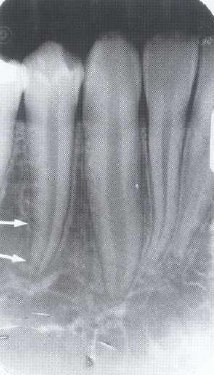

71. What is showing by arrow?

"Lamina Dura" : a thin radiopaque layer of dense bone bounding the tooth socket. It is continuous with the shadow of the cortical bone at the alveolar crest. The presence of an intact lamina dura around the apex of a tooth strongly suggests a vital pulp.

72. What is showing by arrow?

> Periodontal ligament (PDL) • Radiographically seen as a radiolucent line on inside of lamina dura PDL is thinner in the middle of the root and slightly wider near the alveolar crest and root apex average width: 0.5 mm). Position in relation to tooth can determine if lesion is attached to tooth structure (inside PDL) or not (outside PDL). Widening of the periodontal ligament space: Increased width of periodontal ligament space due to inflammation. Etiology: pulp necrosis, root fracture, trauma from occlusion, malignancies, scleroderma (generalized PDL)